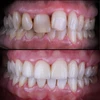

Zirkonyum uygulamalar

Porselen uygulamaları

Laminate veneer